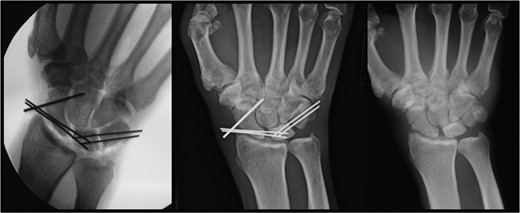

Left: intraoperative image demonstrating K-wires supporting the lunate. Center: postoperative image at 10 months demonstrating the lunate still in proper position with retained hardware. Right: postoperative image at 10 months demonstrating proper positioning of the lunate after removal of hardware.

Postoperative examination revealed a neurovascularly intact right upper extremity. The patient was lost to follow-up until presenting with symptomatic instrumentation 10 months postoperatively. Normal lunate radiographic density on X-rays confirmed revascularization of the lunate (Fig. 3). Clinical evaluation demonstrated a neurovascularly intact, stable carpus without evidence of carpal collapse or arthrosis (Fig. 3). The instrumentation was removed and the patient reported no pain with daily activities and full range of motion when compared with the uninjured left hand.